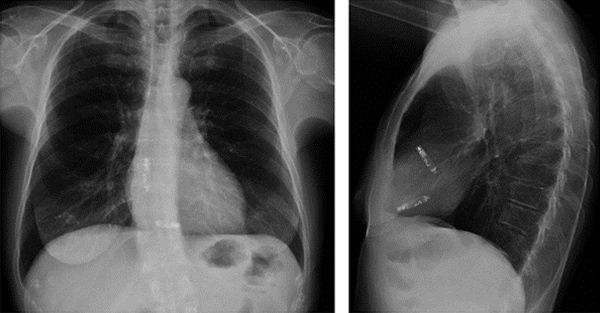

A chest X-ray showing a dual-chamber leadless pacemaker.